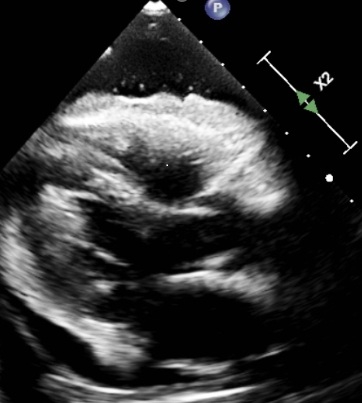

Microbubbles In the Pericardial Space: An Unusual Echocardiographic Finding

Hydropneumopericardium is a term used to describe accumulation of fluid as well as air in the pericardial space. Air or microbubbles in the pericardial space are rare findings typically associated with trauma, invasive procedures, or mechanical ventilation. Less common causes include malignancy, infection, and spontaneous erosion of adjacent structures. Early identification is important, as pneumopericardium can lead to tamponade and have a high mortality rate.

A 79-year-old woman with asthma presented with dyspnea, orthopnea, weight loss, and a right chest wall mass for 7 years. CT image revealed bilateral pleural effusions, a large pericardial effusion, and a right upper lobe soft tissue mass. Transthoracic echocardiography revealed a large pericardial effusion with unusual bright echo densities suggestive of microbubbles, raising concern for potential pneumopericardium. Pericardiocentesis was performed, yielding 400 mL of serous fluid. The drain remained in the place for approximately a week with persistent drainage that tapered slowly. The patient opted against getting a prophylactic pericardial window. Cytology reports came back positive for malignant effusion with suspected primary as malignant breast cancer, that is Estrogen Receptor and Progesterone Receptor positive. She was then started on Anastrozole and discharged to rehab with close follow up with oncology.

Pneumopericardium is most often related to trauma, barotrauma, or procedures such as pericardiocentesis, pacemaker placement, or esophagectomy. Less common causes include malignancy, tuberculosis, aspergillosis, and gastropericardial fistulae. Microbubbles in the pericardial space may be an early sign of air leakage, often preceding overt pneumopericardium. In our case, no communication with airways or gastrointestinal tract was identified on imaging, and no mechanical ventilation was used, ruling out barotrauma or fistulization. The presence of microbubbles may reflect localized necrosis or vascular invasion by tumor, leading to micro-air leak. Given the high mortality of unrecognized pneumopericardium and its potential for tamponade, early recognition of intrapericardial bubbles is critical. This case expands the differential diagnosis of this rare echocardiographic finding and highlights the importance of malignancy as an underlying etiology.